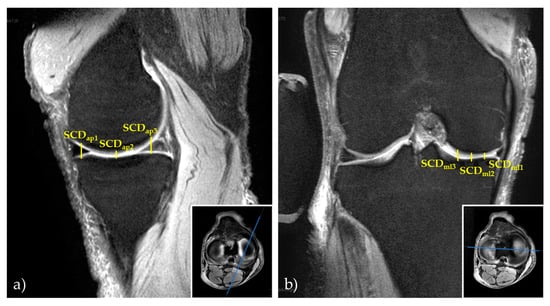

First, the mid-sagittal and mid-coronal images (with respect to the medial compartment) were identified on the Proton Density-weighted fat-saturated sequences. Second, the vertical distances between the tibial and femoral subchondral cortices (subchondral cortical distances [SCD]) were determined as surrogate markers of the medial joint space at three anteroposterior and three mediolateral locations on the mid-sagittal and mid-coronal images. More specifically, the locations were (from anterior to posterior) the centers of the anterior horn, body region, and posterior horn of the medial meniscus and (from medial to lateral) the peripheral, central, and internal intersections following the division of the medial tibial condyle into quarters (Figure 4). These locations are referred to as SCDap1 to SCDap3 (from anterior to posterior) and as SCDml1 to SCDml3 (from medial to lateral).

Figure 4. Example manual 2D reference measurements of subchondral cortical distances in the medial compartment. Visualized are the mid-sagittal (a) and mid-coronal (b) images of the Proton Density-weighted fat-saturated sequences and inset boxes to indicate their orientation. Subchondral cortical distances are indicated by yellow lines as the vertical distances between the femoral and tibial subchondral cortices at three locations along the anteroposterior (SCDap1 to SCDap3 [a]) and mediolateral dimensions (SCDml1 to SCDml3 [b]).